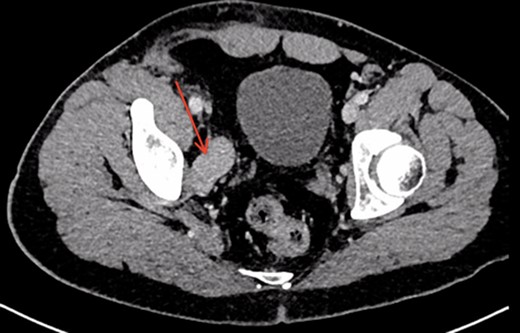

A 26-year-old man was referred to our vascular surgery tertiary referral service from his local hospital with leg size discrepancy (right > left) and prominent right leg varicose veins distally. He had lower urinary tract symptoms (frequency >30 times per day) for a year prior to presentation but had no leg symptoms in relation to his varicosities. His past medical history was of premature birth, as one of triplets, who spent a prolonged period on a neonatal intensive care unit. The patient thought he may have had a deep vein thrombosis in his right leg as a child. An MRI of his right thigh and pelvis demonstrated a 5 cm venous aneurysm (EIV), indenting the bladder, and generalized distal venous dilatation of both deep and superficial veins. He subsequently underwent venography, which confirmed an aneurysmal EIV, with massive collateral dilatation of trans-pelvic veins and complete occlusion of the right common femoral vein (CFV). A concurrent attempt at endovenous stenting was made, but was unsuccessful as the CFV could not be passed with a guide-wire and no alternate route was found possible. Further characterization by CT demonstrated a dilated and tortuous right internal iliac vein (IIV) feeding the aneurysm (Fig. 1). A multidisciplinary decision was made to proceed to operative repair, in light of the patient’s debilitating urinary frequency from the mass effect of the aneurysm. Pre-intervention venous severity scoring was not pursued as the patient’s symptoms were only bladder-related. The patient underwent an open aneurysmectomy via a Rutherford-Morrison incision, with concurrent right retrograde ureteric stent placement. Intra-operatively, a wide-necked aneurysm was confirmed to arise from the EIV (Fig. 2) in a saccular fashion. The aneurysm was clamped at the neck and closed with 3-0 Prolene (Ethicon, Inc., New Jersey, USA) leaving a normal calibre EIV (Figs 3 and 4). The IIV remained patent at the end of the procedure and a venous bypass was not performed. The patient recovered well post-operatively and was discharged home four days later, with removal of the ureteric stent prior to discharge. He has been followed up 6-monthly since and remains well at 2 years’ post-operatively. CT venogram has shown a good post-operative result, with no residual aneurysm (Fig. 5). The patient’s pre-operative lower urinary tract symptoms have improved. He did not develop any leg symptoms.

Post-operative CT scan demonstrating no evidence of residual aneurysm, or bladder compression. A residual dilated and tortuous collateral vessel remains communicating between the right internal iliac vein and right common femoral vein (red arrow).